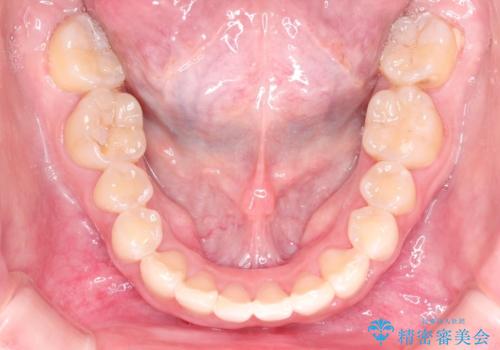

- ハーフリンガル

- 1年8ヶ月

- 上顎の両側第1小臼歯抜歯による抜歯矯正を計画した。

上顎の抜歯により上の前歯の位置を大幅に後ろに下げることができます。